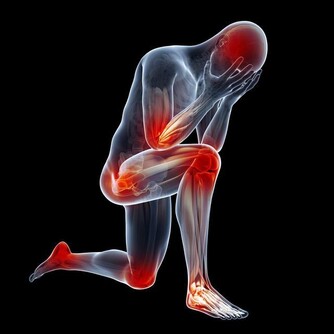

可如果我們的肝臟出現了病變,一開始我們並不能感受到明顯的疼痛。

如果肝臟到了疼痛難忍的時候,那就為時已晚了。